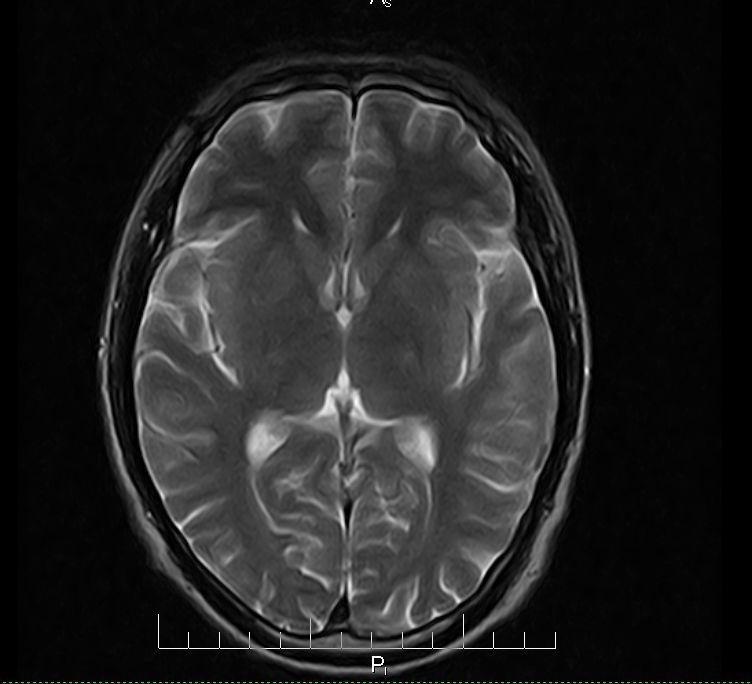

标题: MRI2379:30岁,男,癫痫10年,请各位看一下;CT示:左颞叶钙 [打印本页]

标题: MRI2379:30岁,男,癫痫10年,请各位看一下;CT示:左颞叶钙

左颞叶区见不规则点状混杂信号影

考虑血管畸形

支持2楼 左颞叶区见不规则点状混杂信号影,考虑动静脉畸形。

考虑左侧颞叶脑血管畸形(avm)。

考虑左侧颞叶脑血管畸形(avm)。----t1低等高混杂信号,t2等高信号周边较多流空血管影[冠状位明显],mra左侧大脑中动脉受压,远侧聚集.